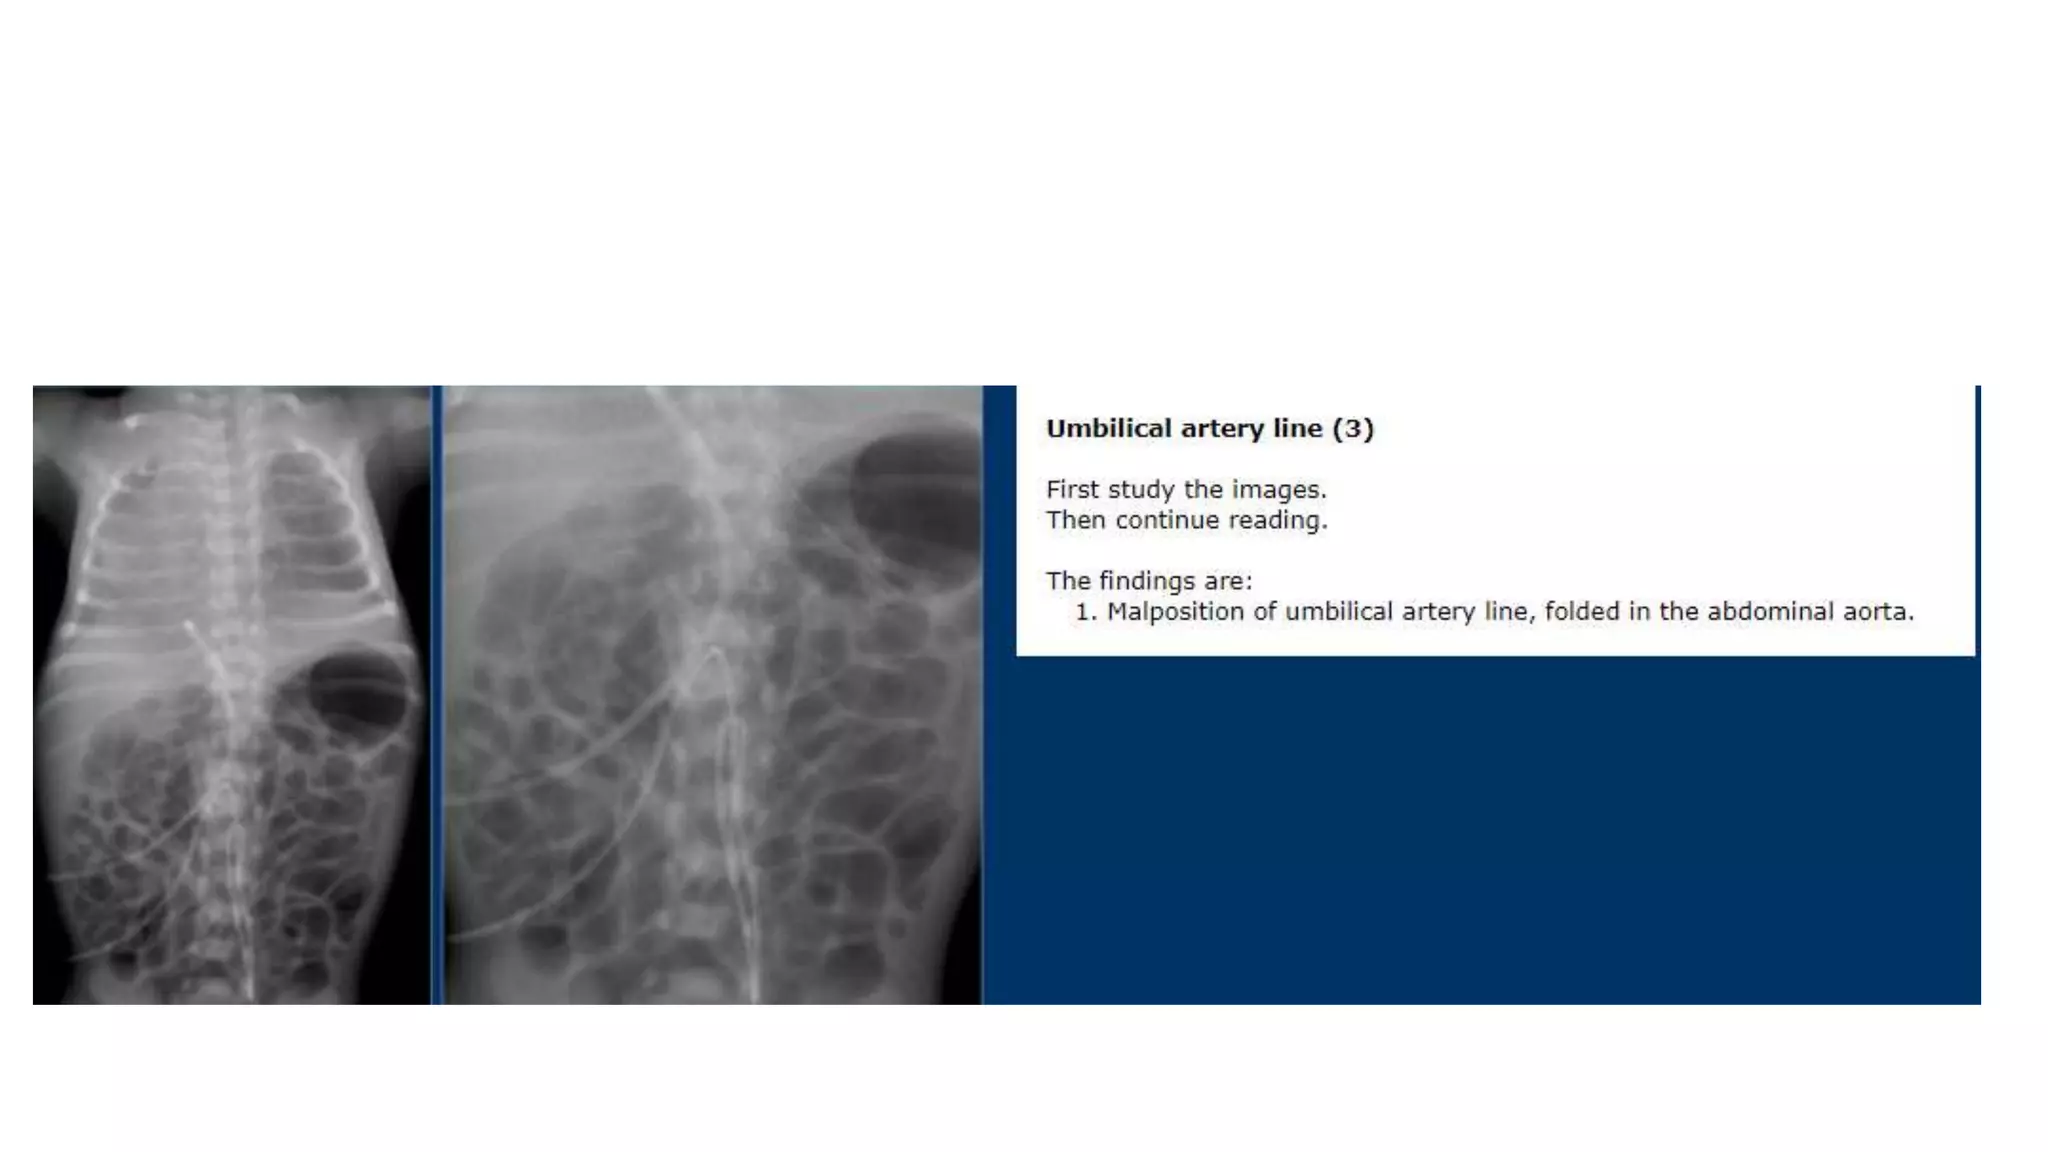

This document provides an overview of neonatal chest x-rays, including when they should and should not be performed, what a normal x-ray looks like, common positions of tubes and catheters, and common causes of respiratory distress in neonates. It discusses the appearance of a normal chest x-ray as well as conditions like respiratory distress syndrome, transient tachypnea of the newborn, meconium aspiration syndrome, and pneumonia. Surgical conditions like diaphragmatic hernia and esophageal atresia are also reviewed.